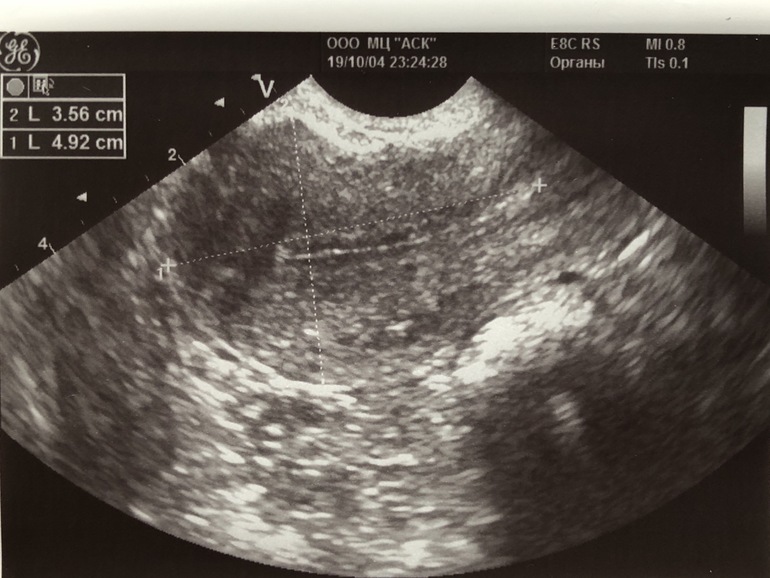

Аденомиоз могут на УЗИ заподозрить по ячеистой структуре миометрия (ячейки- это и есть лакуны в миометрии, заполненные кровью).

А у меня на фото есть ячеистые структуры миометрии?

Мне заметны ячейки, и в заключении УЗИ указано о наличии диффузных (то есть равномерно распределенных) изменений миометрия.

И одной из причин аденомиоза и эндометриоза также могут быть неполадки с иммунитетом или с гормонами, ну и, как я ранее написала, по причине разного рода вмешательств оперативных.